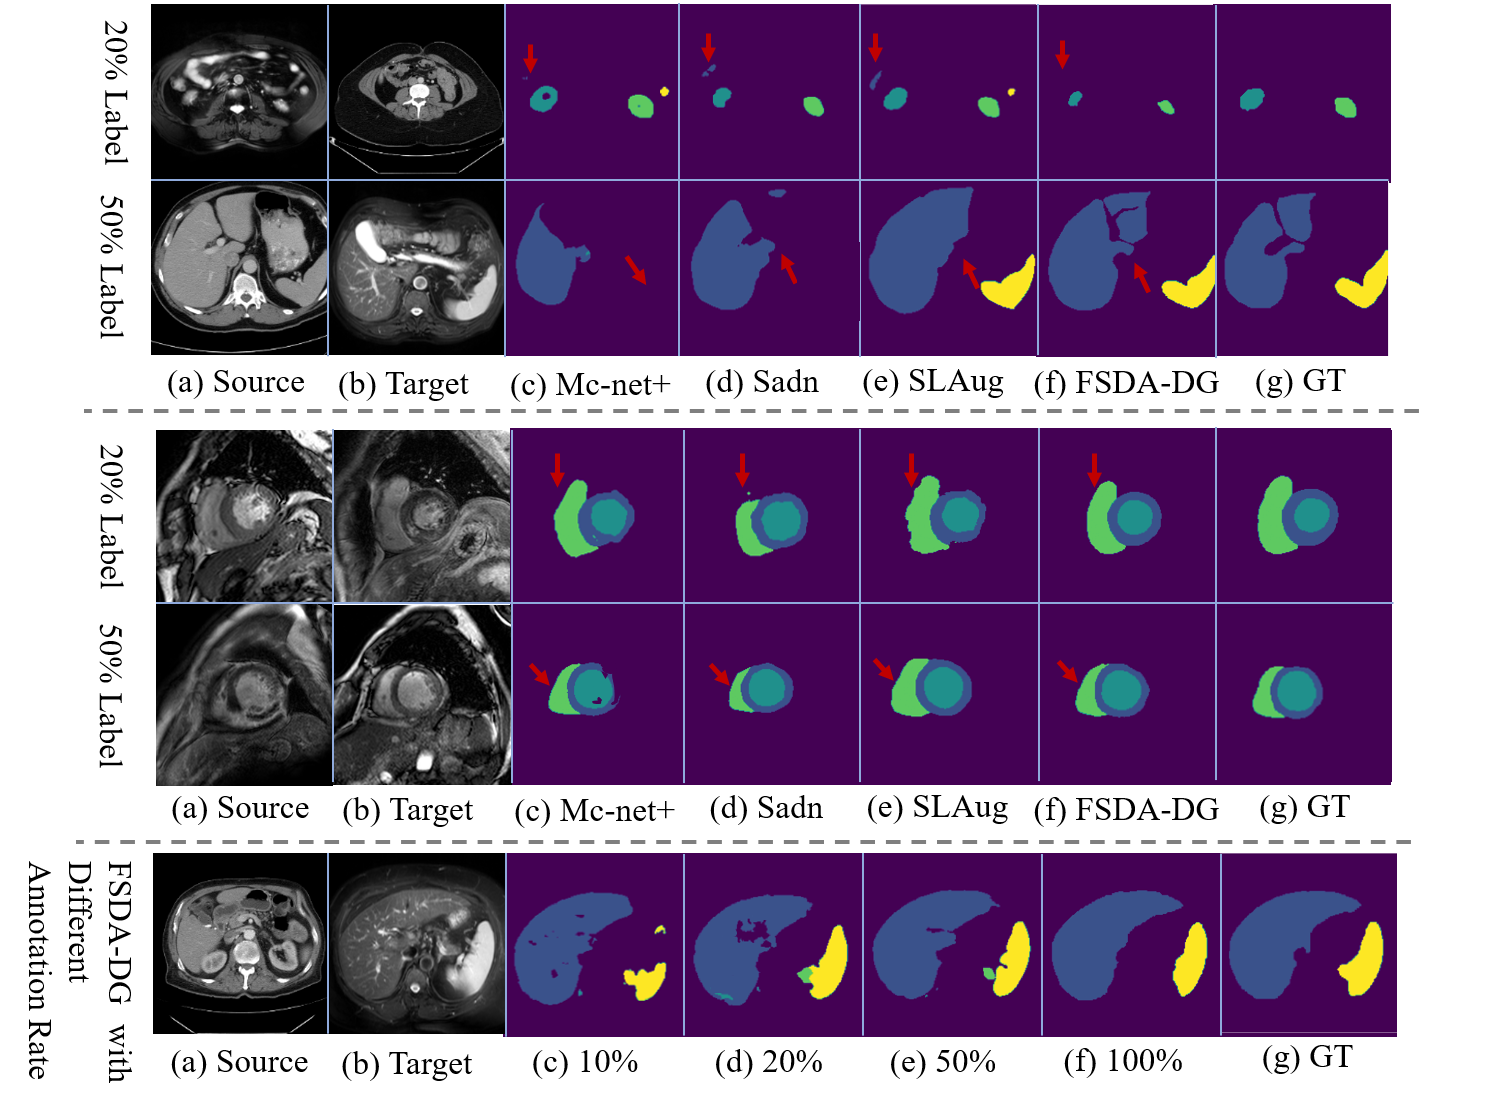

4.3.2 Visual Comparison

Fig. 7 presents the segmentation results of SSL and DG methods, including MC-Net+, Sadn, SLAug, and FSDA-DG. Fig. 8 presents the segmentation results of SSLODG methods on different target domains and at varying labeling rates. These visual comparisons demonstrate that FSDA-DG accurately segments target regions of varying sizes, shapes, and spatial locations. The boundaries delineated by FSDA-DG are consistently sharper and more precise than those from competing methods, highlighting its superior boundary prediction capabilities.